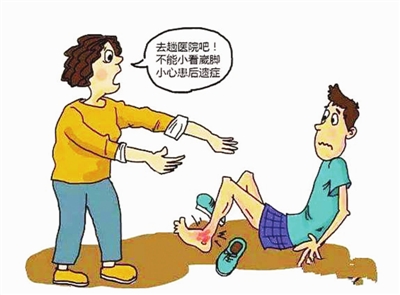

3、别人的错误你是否也曾经犯过呢?

门诊遇到一“熊孩子(调皮的学生)踢球崴脚了,休息片刻,为荣誉继续征战,踢得不亦乐乎;结果踝关节肿了,涂了活络油,敷了热毛巾,揉了踝关节。第二天踝关节更肿了、更痛了,淤青了,硬撑着走了1公里路到医院看病。

“熊孩子”:医生,我是不是很勇敢,都能够从学校走路过来,应该不会很严重吧?

医生:查了一下体,外踝尖压痛明显,去拍个片子吧。

“熊孩子”:OH,my god!有这么严重吗?还要拍片。我以前扭伤的时候,贴两天膏药就好了。

医生:孩子,每次扭的姿势不一样,扭的部位不一样,扭的程度不一样,表现出来也会不一样的。踝关节扭伤最常见第五跖骨基底部骨折、外踝撕脱骨折,这两种往往忍着点还是能够拐着进诊室的。